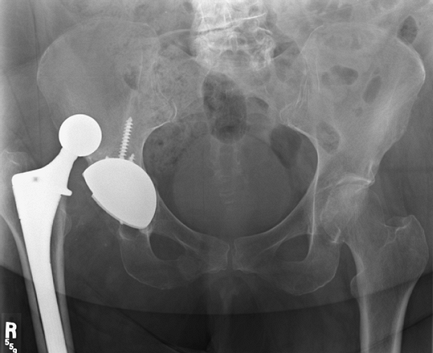

![]() |

|

Figure 2-12 Anteroposterior pelvis radiograph demonstrating a dislocated total hip arthroplasty.

Figure 2-13 Anteroposterior pelvis radiograph demonstrating appropriate acetabular abduction. A, abduction angle of acetabular component.

A common cause of early dislocation is component malposition. AP

radiograph should demonstrate approximately 45 degrees of abduction (Fig. 2-13).

Assessment of acetabular anteversion can be obtained from a true

lateral radiograph. Appropriate acetabular component anteversion is 10

to 30 degrees. Occasionally CT scan to directly demonstrate femoral and

acetabular component position may be required.